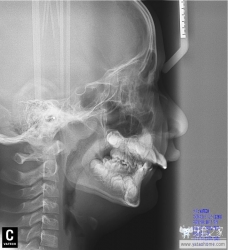

凹面型,生活中常把这种情况称之为“地包天”,(貌似一个叫杨子的就被恶毒地称为“鞋拔子教教主”,

还把这样称呼他的记者告到中宣部,汗一个)也有两种,包括上颌骨发育不足或者下颌骨发育过度。我们这个病例展示的是父子两人均为凹面型,

儿子的凹面型更为严重,需要正颌外科治疗。“地包天”是一种较为严重的牙颌畸形,对面型的影响较大,在治疗方面目前采用的是序列跟踪治疗。